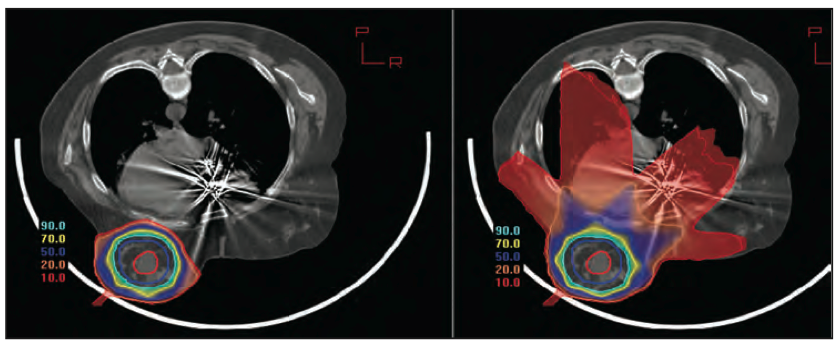

鉴于乳腺癌成为全球第一大癌症,特别是在上海等大型城市,乳腺癌已连续20多年高居女性恶性肿瘤发病率榜首,放射治疗是乳腺癌多学科联合治疗的重要手段之一,女性患者“保乳”“护心”需求大,粒子放疗精准、副作用小,故上海市质子重离子医院近期已将乳腺癌纳入粒子放疗重点病种管理。目前,医院已累计采用质子射线放疗乳腺癌患者345例,其中随访时间满6个月的患者244例,中位随访时间24个月,患者两年总生存率达100%,两年无瘤生存率达97%,随访仅观察到皮肤色素沉着等轻微副反应,未见常规光子放疗可能出现的对心脏的相关毒副反应。